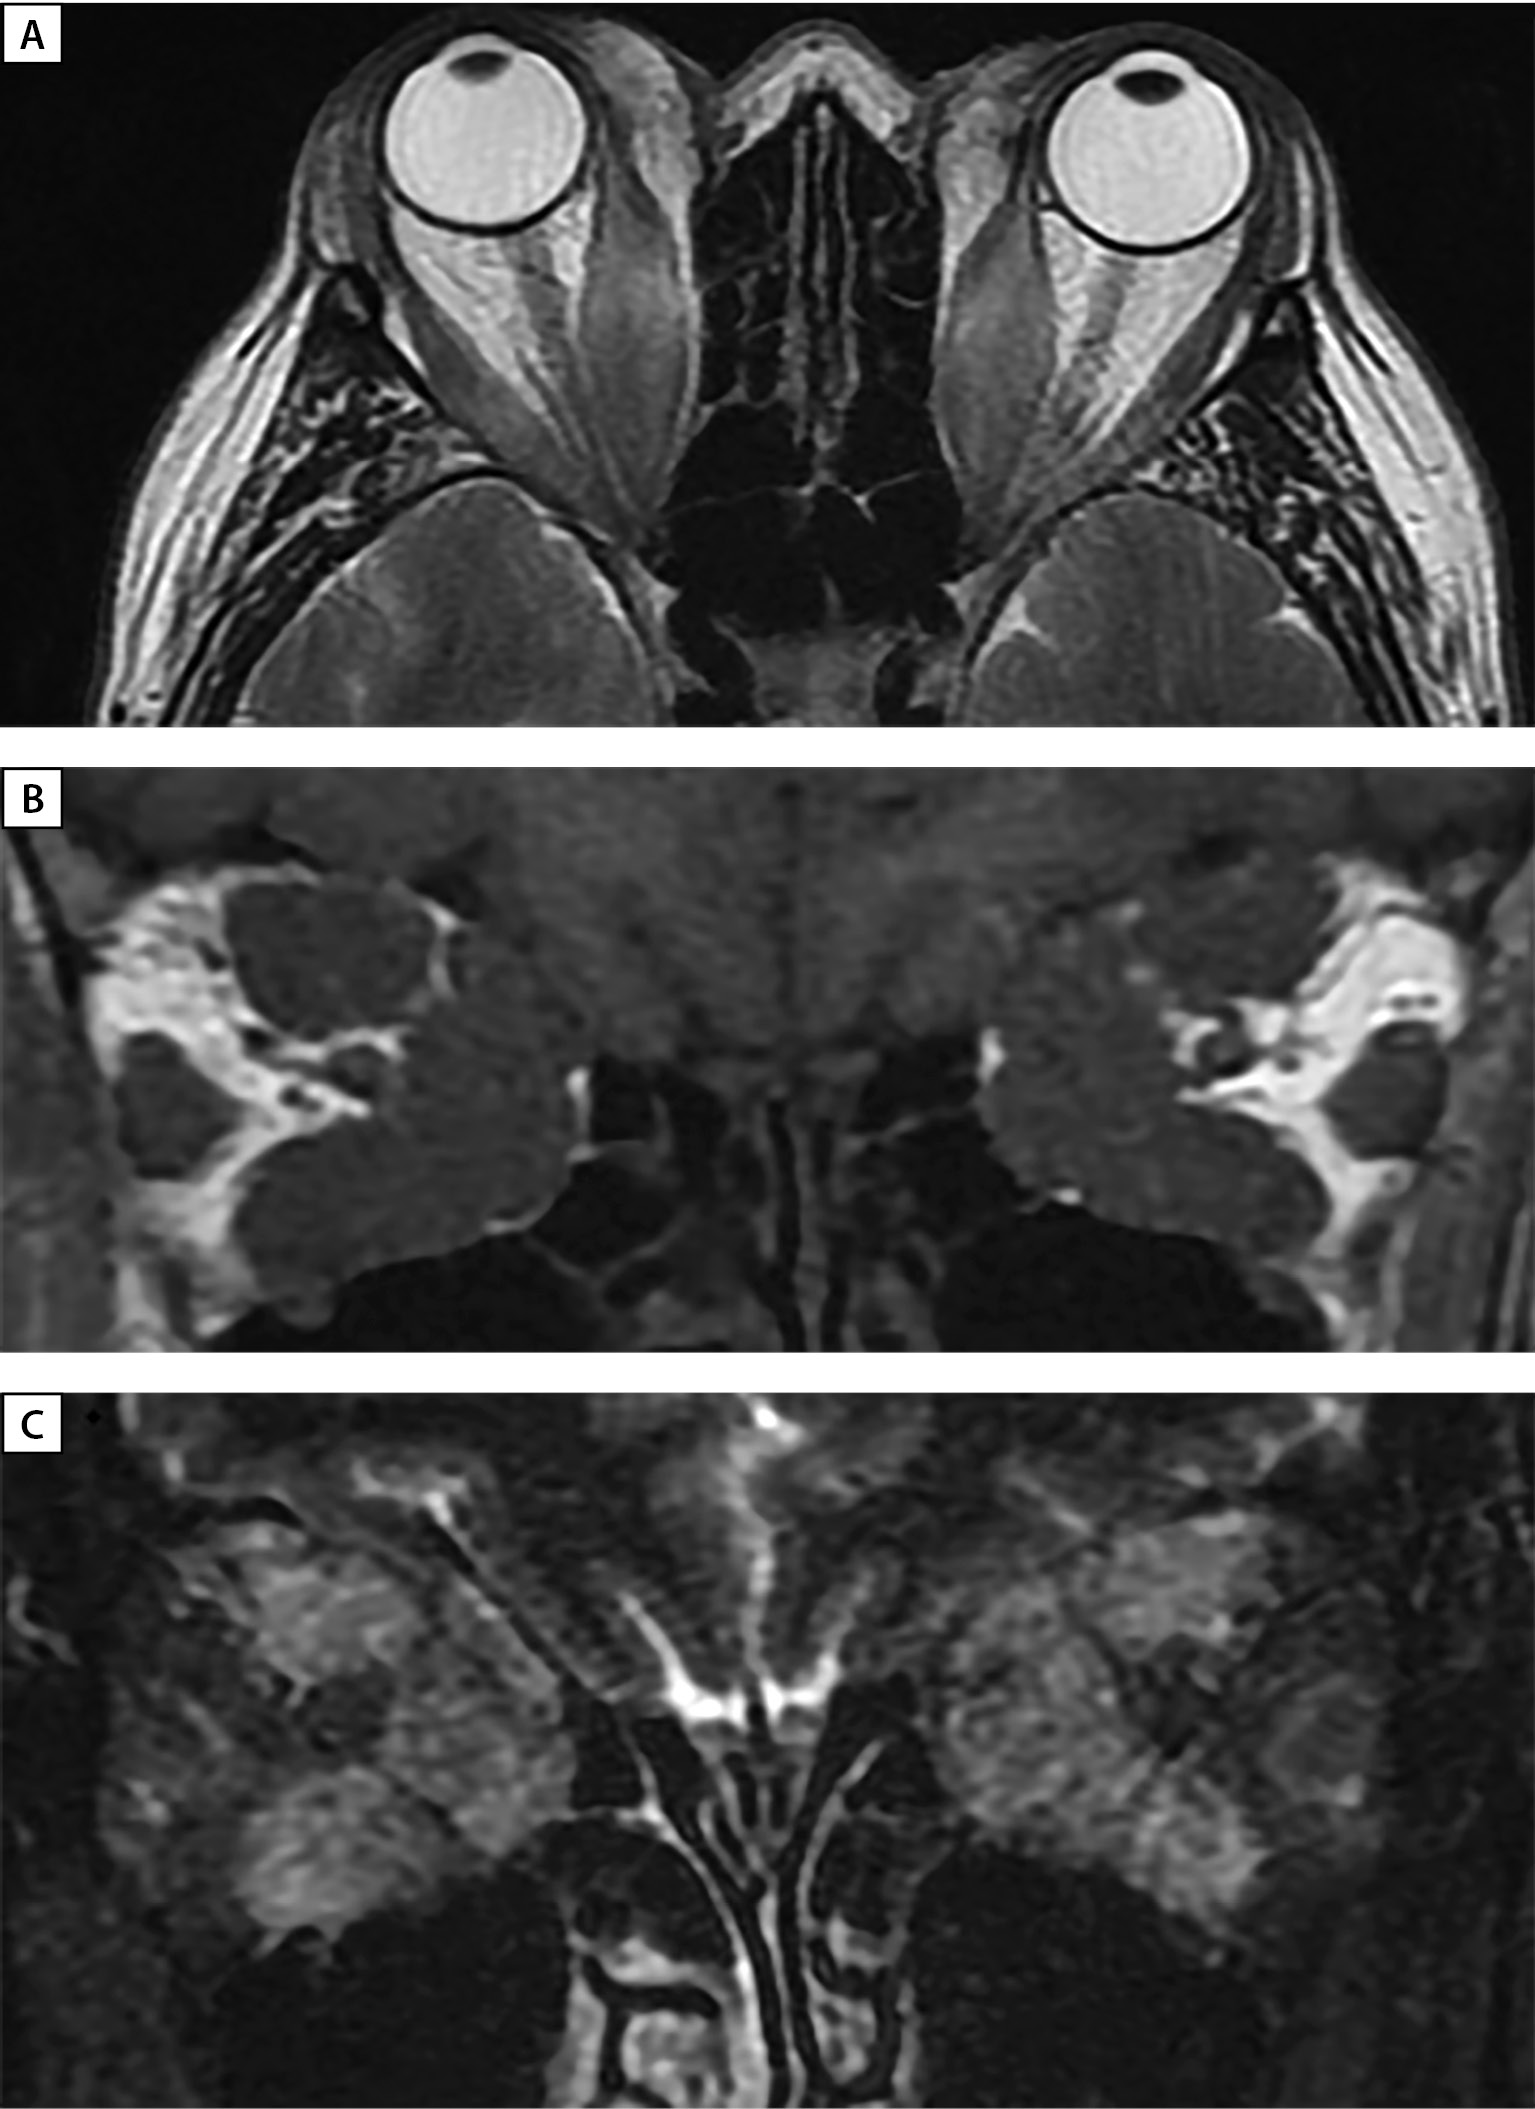

В августе 2022 г. при очередном обследовании в ФГБУ «НМИЦ эндокринологии» на фоне приема левотироксина натрия в дозе 150 мкг/сут сохранялся эутиреоз. Данных за рецидив папиллярного рака не получено (тиреоглобулин — 0,014 нг/мл, антитела к тиреоглобулину — 18,49 МЕ/мл, норма 0–115) (рис. 7). По данным МРТ орбит: утолщение, жировая трансформация ЭОМ, умеренный отек нижних прямых и правой верхней прямой мышцы. Уплотнение, незначительный отек РБК с обеих сторон (рис. 8 А, В). По заключению офтальмолога: ЭОП неактивная фаза (CAS=1). Острота зрения обоих глаз=1,0. Состояние после пульс-терапии ГК в суммарной дозе: метилпреднизолон 7750 мг + преднизолон 5100 мг (декабрь 2020 г. — март, июль–август 2021 г.). Пациентка продолжает наблюдаться в ФГБУ «НМИЦ эндокринологии» и в ФГБНУ НИИ ГБ им. М.М. Краснова.

Рисунок 8. МРТ орбит через 16 месяцев после глубокой латеральной КДО с двух сторон.

А — аксиальная проекция — выход мягких тканей орбиты в область латеральной остеотомии,

отмечается уменьшение в объеме ЭОМ.

В — корональная проекция, режим Т2 STIR c жироподавлением отсутствует отек ЭОМ и РБК.